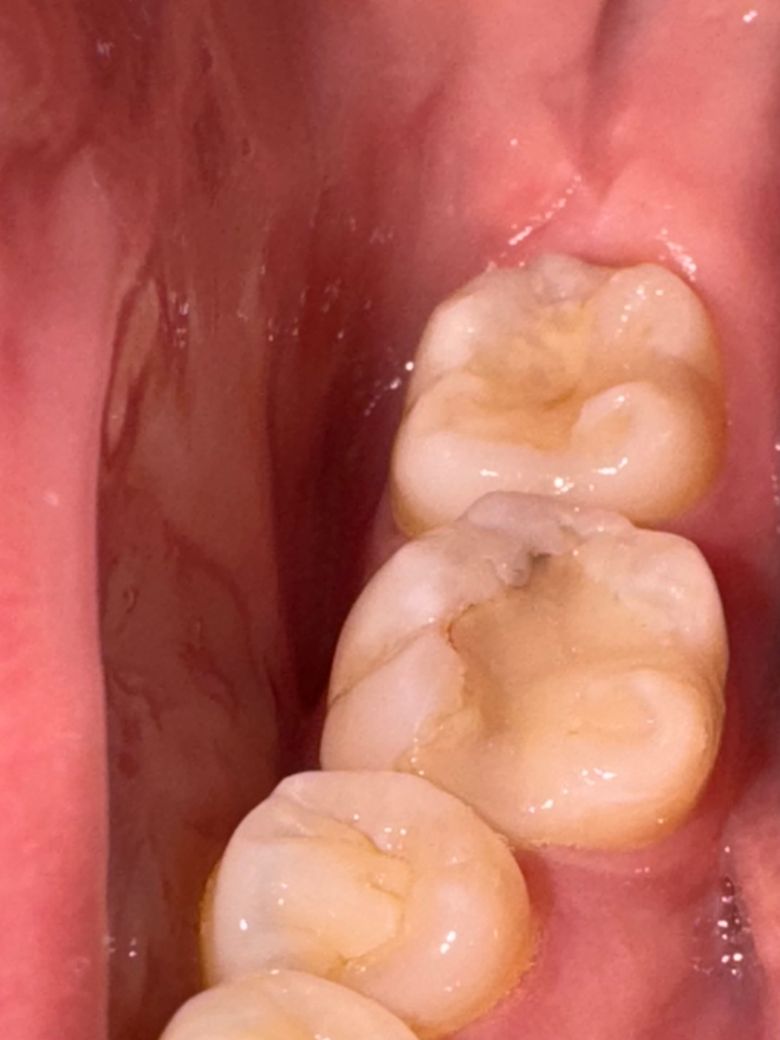

다시 인레이 한 이후에는 색이 괜찮았는데, 오늘 양치하면서 거울보니 사진과 같이 경계가 거뭇하게 보입니다.

사진으로 봤을 경우에는 보철물과 치아 사이의 경계 부위에 틈이 생긴 것으로 보입니다. 보철물과의 경계물에 틈이 있게 되면 해당 부위에 충치가 더 진행될 수 있으니 가능하면 재치료를 하는 것이 좋습니다. 해당 부위에 레진 등으로 치료를 하는 방법도 있습니다.

수복물과 치아사이에 틈이 변색 혹은 충치가 생긴 것으로 보입니다. 아무래도 제거 후에 재치료를 받으셔야겠습니다.

사진상 보이는 검은색은 단순 이물질로 인한 변색일 확률이 높아 보입니다. 다만, 경계에서 음식물이 잘 낀다면 재치료를 해주거나 적어도 인레이를 다듬어주는 것을 추천합니다.